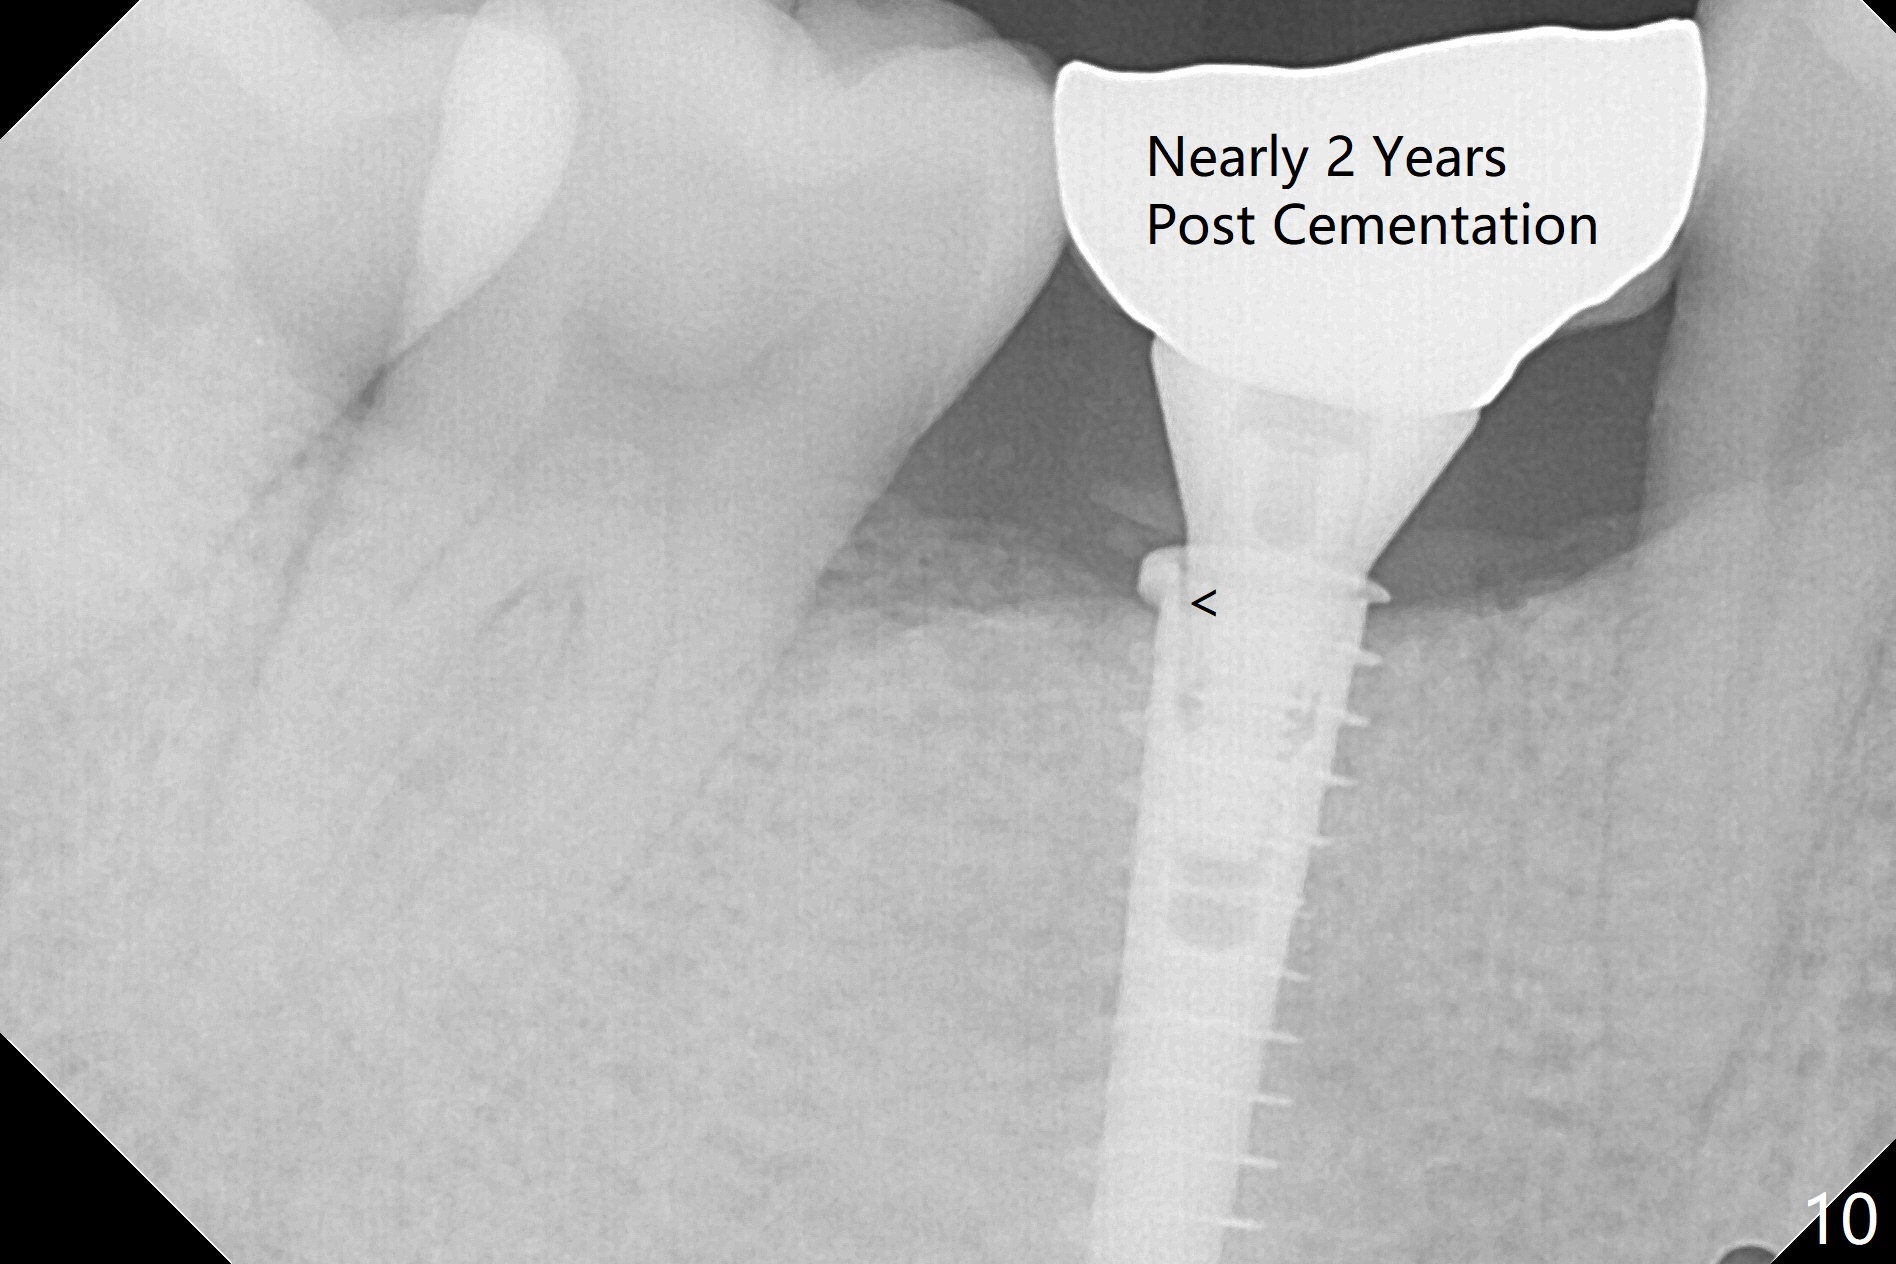

The patient returns 5.5 months postop for final restoration. The implant appears to have osteointegrated (Fig.8). When the locked in provisional is removed, the gingiva bleeds (Fig.9). She will return in 2 weeks. The abutment remains incompletely seated nearly 2 years post cementation (Fig.10).